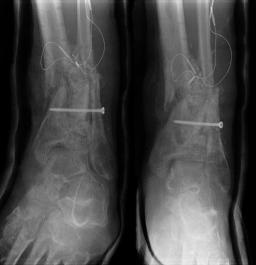

Post-skin graft & bone infuse surgery X-Rays of the left & right ankle

These x-rays were taken four weeks after surgery where grafts of skin were used to cover the open wound on Liam's left ankle. Dr. Gottlieb

infused bone material into the tibia gap of the left ankle. The 3 cm fragment in the left ankle does not appear to have fused or to be

obstructing normal movement so no immediate plans exist to modify the remaining bone fragments. Following these x-rays it is the plan to

remove the right ankle screw that was misplaced by Dr. Keller.